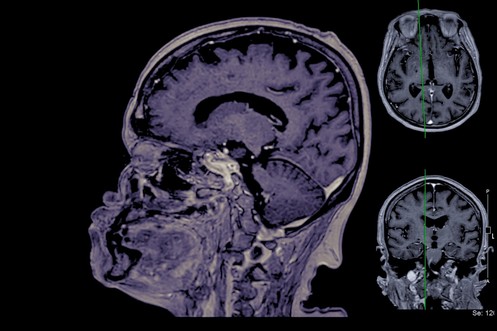

Darum gibt's neue Hoffnung im Kampf gegen Alzheimer

von Bruno Knellwolf

Neue Therapie könnte Alzheimer-Verlauf verlangsamen